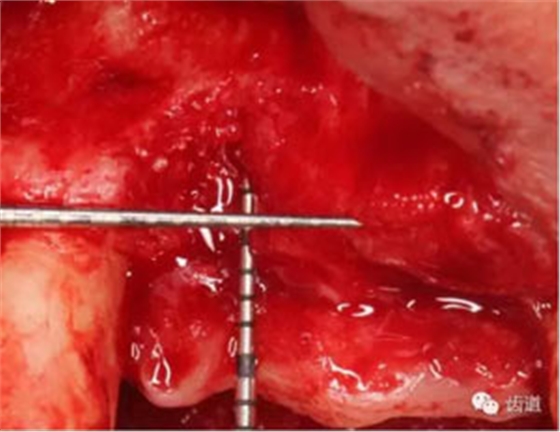

患者對(duì)美觀要求較高,與患者溝通后,擬定采用骨環(huán)技術(shù),同期種植并增加骨寬度和高度。

患者不愿才用自體骨移植,遂建議采用同種異體骨骨塊(皮質(zhì)骨)進(jìn)行骨環(huán)手術(shù)。 種植手術(shù):